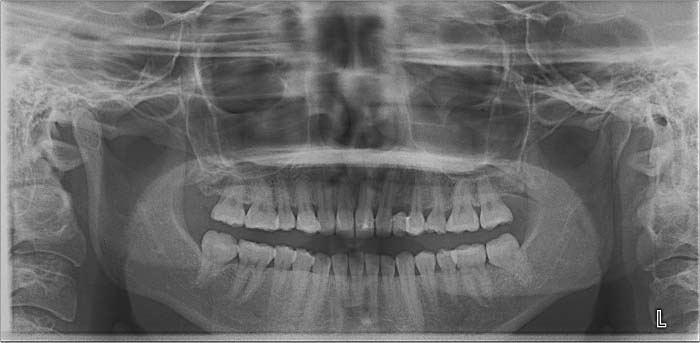

噛み合わせ治療の症例24

スプリント使用後、

補綴治療をした症例

初診日 2023年10月12日